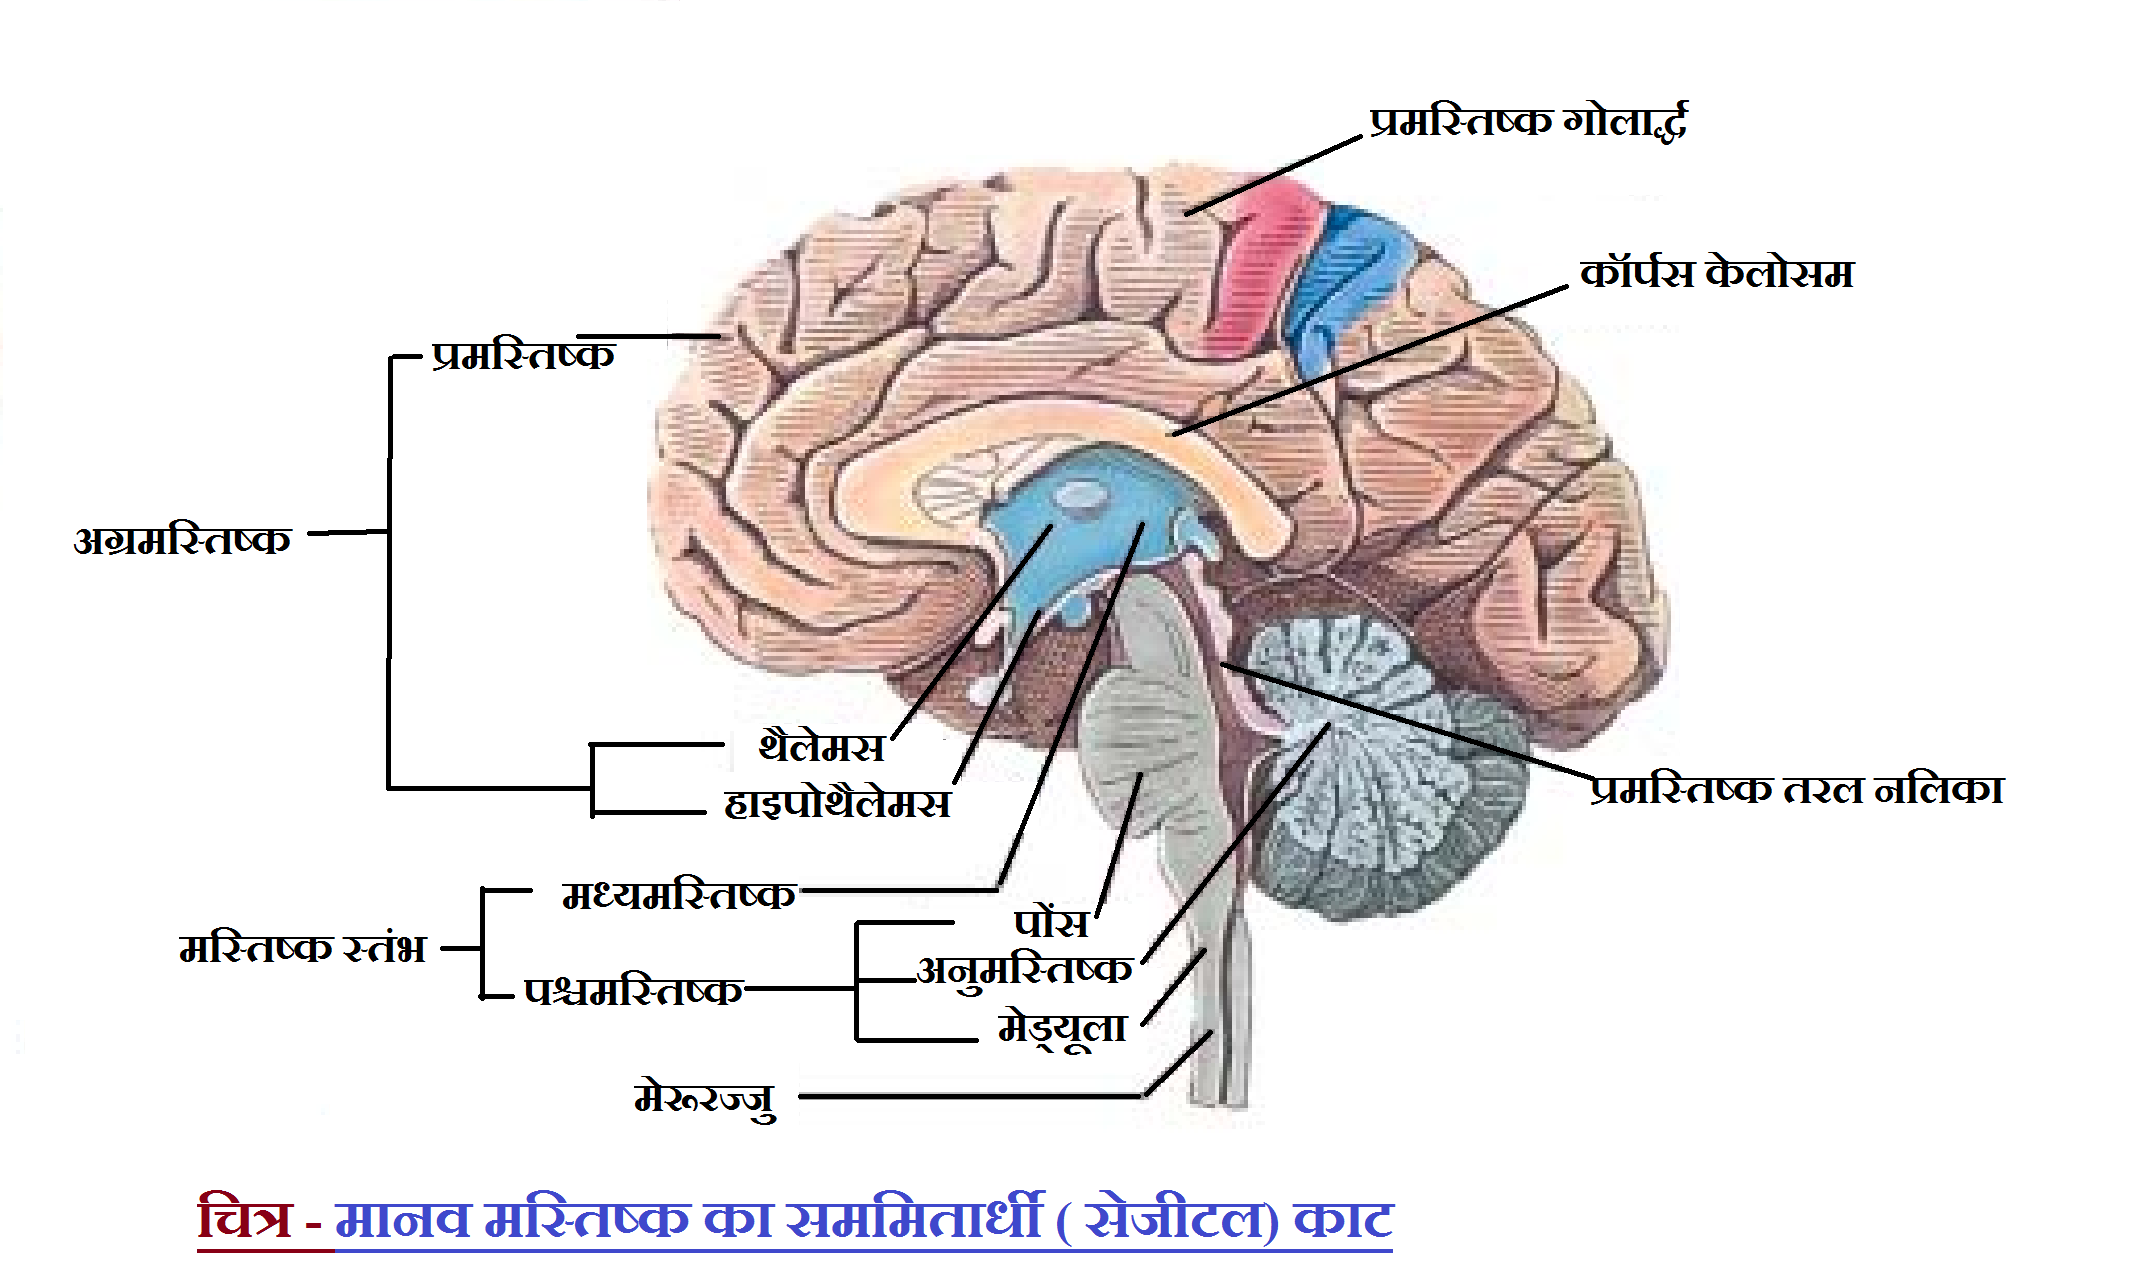

Search q draw e0 a4 ae e0 a4 be e0 a4 a8 e0 a4 b5 e0 a4 ae e0 a4 b8 e0 a5 8d e0 a4 a4 e0 a4 bf e0 a4 b7 e0 a5 8d e0 a4 95 e0 a4 95 e0 a4 be e0 a4 a8 e0 a4 be e0 a4 ae e0 a4 be e0 a4 82 e0 a4 95 e0 a4 bf e0 a4 a4 e0 a4 9a e0 a4 bf e0 a4 a4 e0 a5 8d e0 a4 b0 e0 a4 b9 e0 a4 bf e0 a4 82 e0 a4 a6 e0 a5 80 tbm isch (फाइल का प्रकार jpg)

3